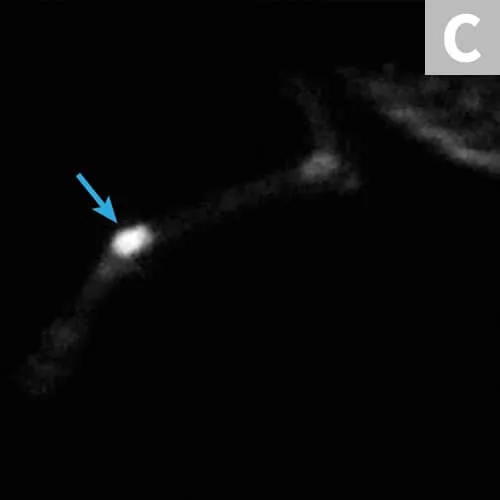

(A) Radiograph of a distal radial osteosarcoma. Centered at the distal metaphysis of the radius, there is evidence of permeative and moth-eaten lysis. There is also concurrent ill-defined periosteal proliferation consistent with an aggressive bone lesion. (B) CT scan of distal radial osteosarcoma in the same patient. Coronal view of limb in bone window. There is more evidence of geographic bone lysis and evidence of periosteal proliferation. Consistent with an aggressive bone lesion. (C) Bone scan of the distal radial osteosarcoma in the same patient. Note the increased uptake of radiopharmaceutical in the distal radius of the patient (arrow).